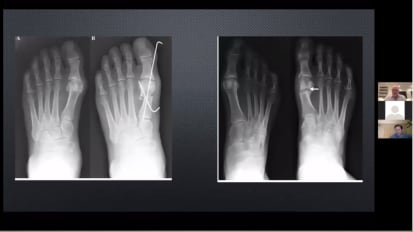

PROSTEP™ MICA™ MIS HALLUX VALGUS CORRECTION

PROstep™ MIS: A detailed look at minimally invasive surgery for hallux valgus [AP-013729]

Dr. W. Hodges Davis and Dr. Peter Mangone discuss modern day minimally invasive tools and the MICA™ technique for hallux valgus deformity